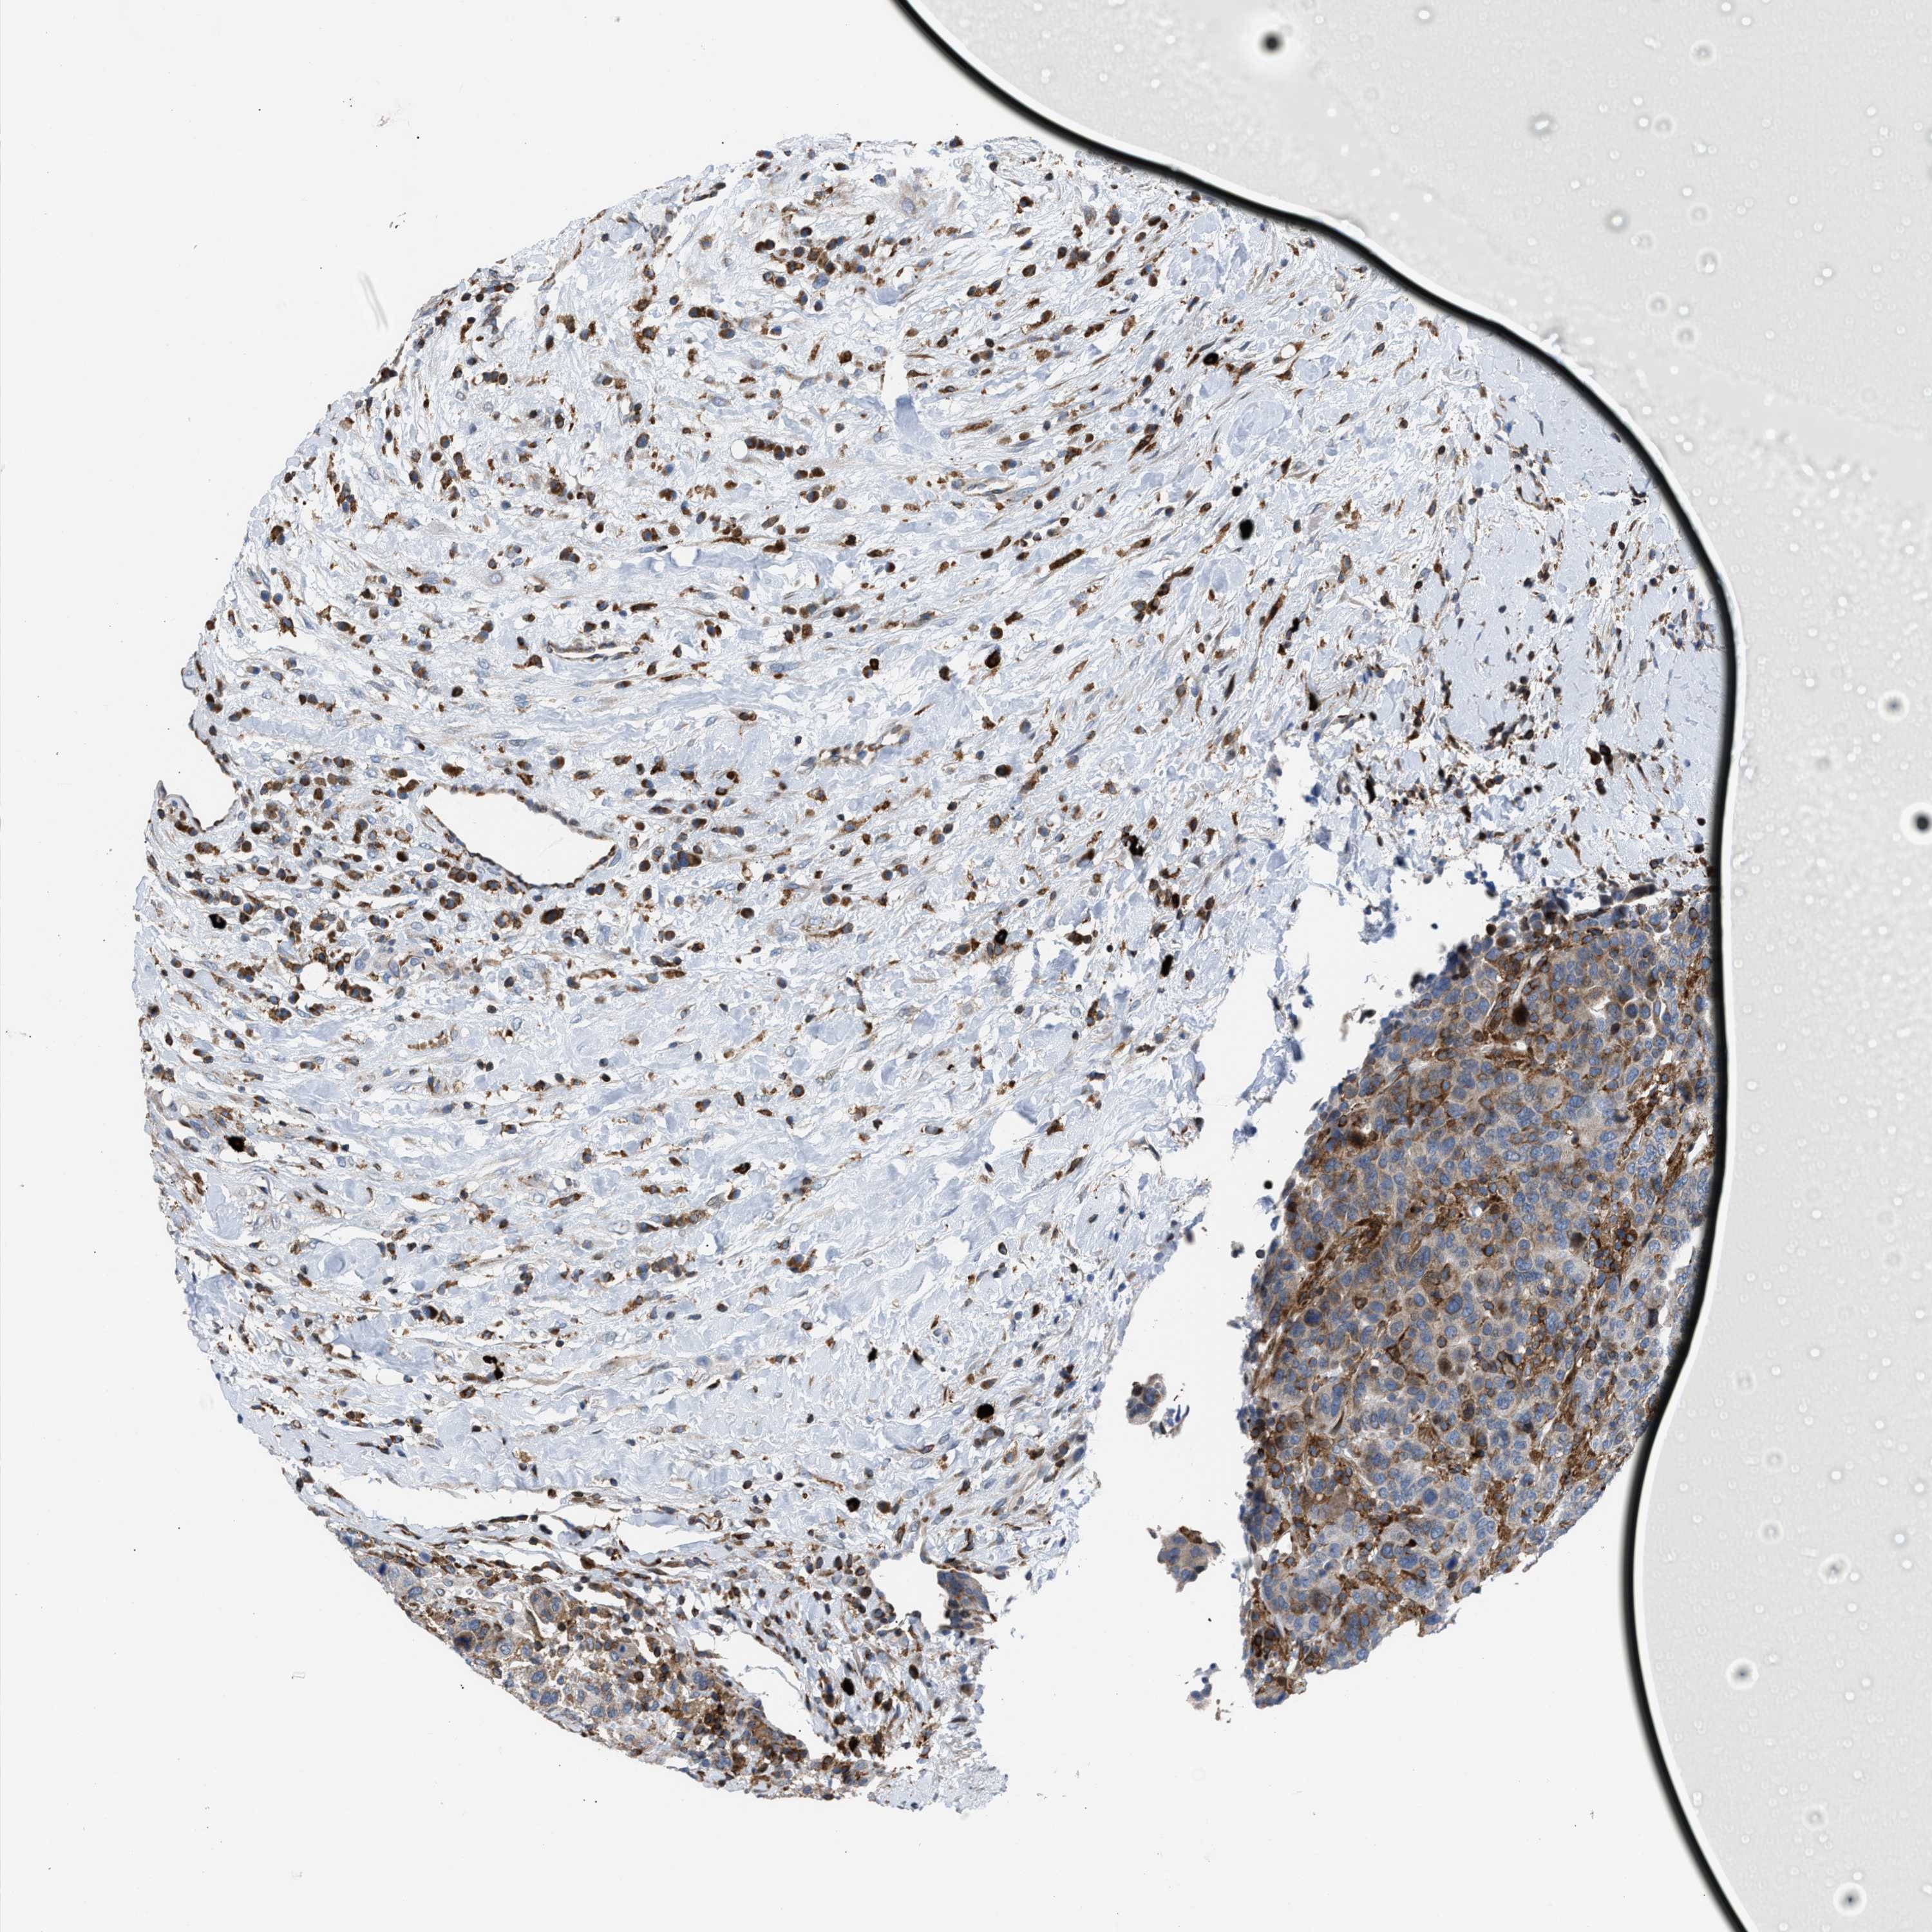

BRCA TCGA BRCA VALIDATION PROTEIN EXPRESSION

Breast cancer

Human cancer